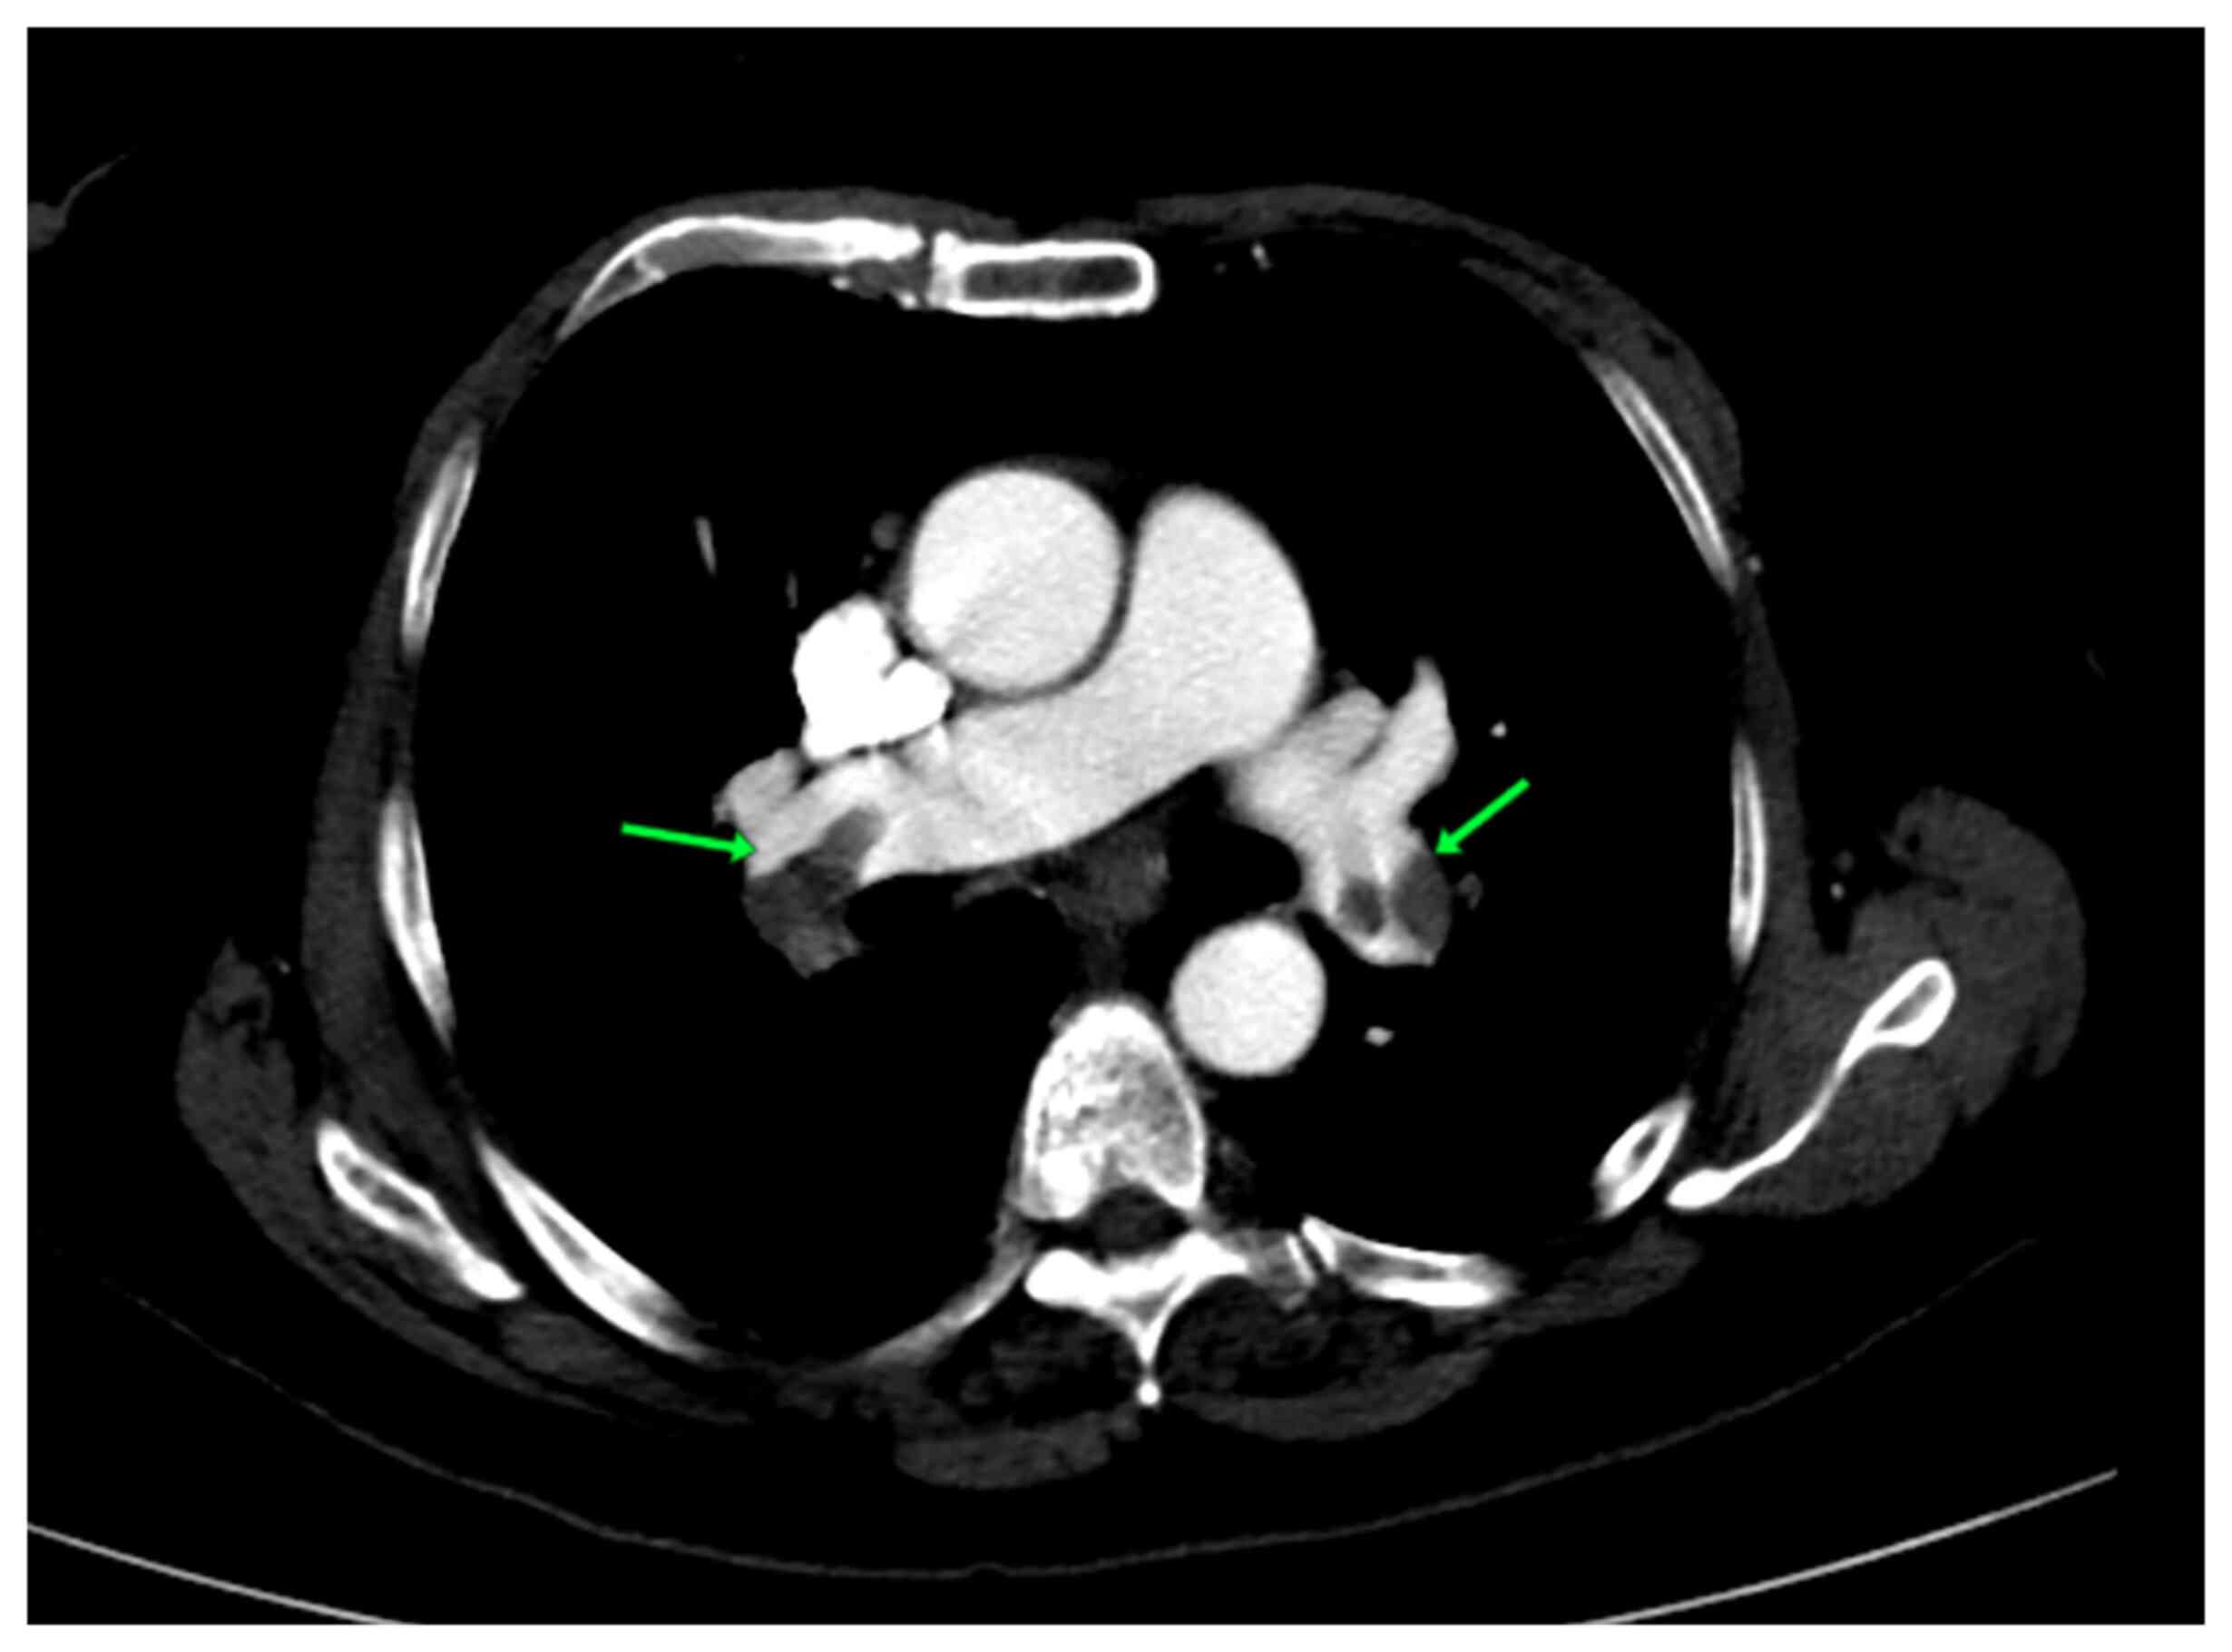

A blood examination was conducted and revealed a normal blood composition. The troponin I test (0.03 ng/ml), renal function and liver function tests were within the normal ranges, while the C-reactive protein (98.80 mg/l) (normal range, ≤5 mg/l) and D-dimer (7599.9 ng/ml) (normal range, ≤500 ng/ml) levels were abnormal. An ECG revealed a biphasic inversion of the T wave in precordial leads in the pain-free interval. A minimal elevation of the ST segment, no precordial Q waves, and one ventricular extrasystole were also observed in the ECG (Fig. 1). The echocardiography revealed a moderate dilatation of the right ventricle, moderate tricuspid regurgitation, inter-ventricular septum flattening (D shape), and positive McConnell's sign. A coronary angiography was performed and this did not reveal any notable findings (Fig. 2). There was no critical stenosis of the proximal LAD coronary artery. A computed tomography pulmonary angiography revealed an acute pulmonary embolism (Figs. 3 and 4). Therefore, all the results supported the occurrence of pseudo-Wellens syndrome. The Thrombolysis in Myocardial Infarction (TIMI) score was equal to one and revealed a low risk of adverse cardiac issues (Table I). The score was determined by the occurrence of only a marked change in her ECG scan.

Figure 3

Computed tomography pulmonary angiography, axial section, indicating filling defects in both right and left pulmonary arteries and acute pulmonary embolism (green arrows).